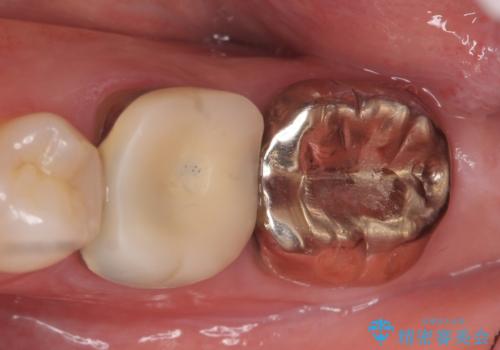

- 左下の奥歯でものを咬むと痛むので診て欲しいといらっしゃった方の症例です。

左下6、7番目の歯に根尖病変を認めたため、再根管治療後、オールセラミッククラウンによる補綴を行いました。